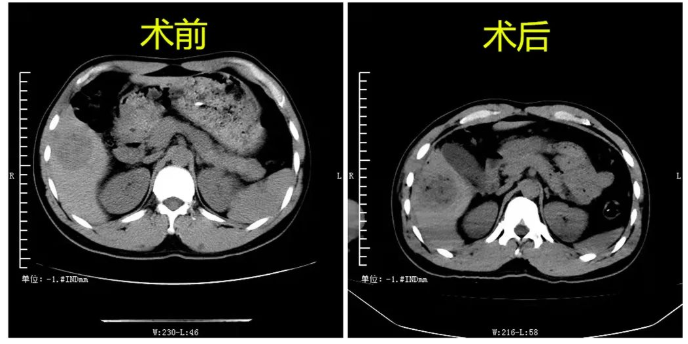

术后立即用CT观察,看到患者肿瘤中心出现多个小气泡影,肿瘤周围呈低密度。4月22日进行CT复查,肿瘤已基本坏死。同时患者最后病检结果为肝细胞性肝癌,跟术前诊断符合,属微波消融技术治疗的适应症。